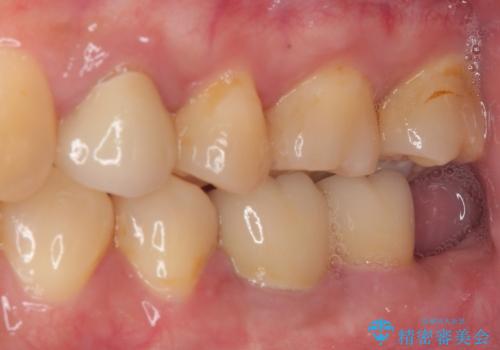

- 奥歯に物が挟まるとのことで来院された患者様です。

レントゲン写真より、奥歯2本に大きなむし歯があることが分かりました。

手前の歯はセラミックインレーで、奥の歯はオールセラミッククラウンにて治療を行うこととしました。

むし歯の範囲は大きかったですが、事前の症状もなく、処置後も一切の痛みなく快適に過ごすことができています。